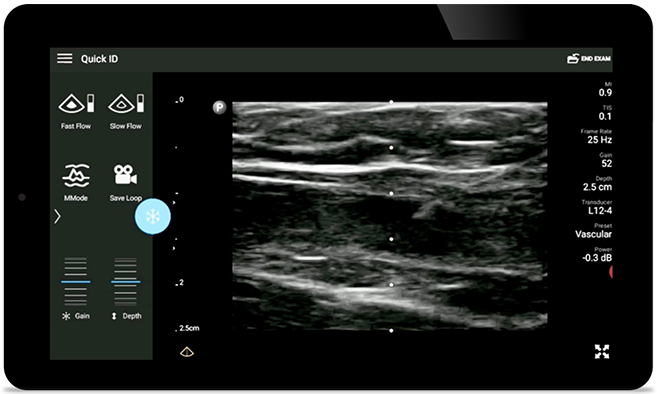

Mniej powikłań związanych z zakładaniem wkłuć centralnych

Wykonywanie wkłuć centralnych pod kontrolą ultrasonografii poprawia ich precyzję i bezpieczeństwo.